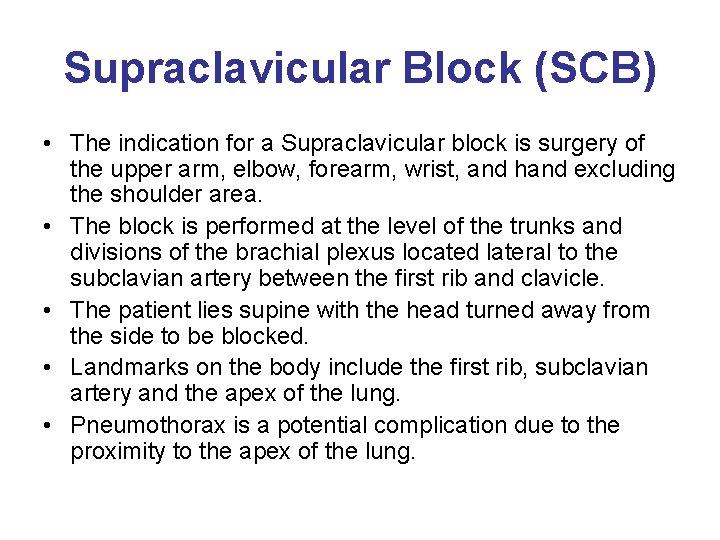

Supraclavicular Block (SCB) • The indication for a Supraclavicular block is surgery of the upper arm, elbow, forearm, wrist, and hand excluding the shoulder area. • The block is performed at the level of the trunks and divisions of the brachial plexus located lateral to the subclavian artery between the first rib and clavicle. • The patient lies supine with the head turned away from the side to be blocked. • Landmarks on the body include the first rib, subclavian artery and the apex of the lung. • Pneumothorax is a potential complication due to the proximity to the apex of the lung.